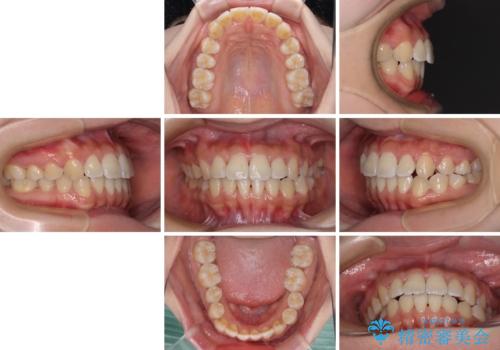

軽微な歯列不正をワイヤー矯正で整える

- 上顎歯列と下顎前歯の叢生を気にして来院された患者様です。

上顎からワイヤー矯正を開始し、終了間際から下顎前歯の叢生解消するよう計画しました。

部分矯正でしたが、咬み合わせに違和感が出ることなく気になる部分を改善させることができました。